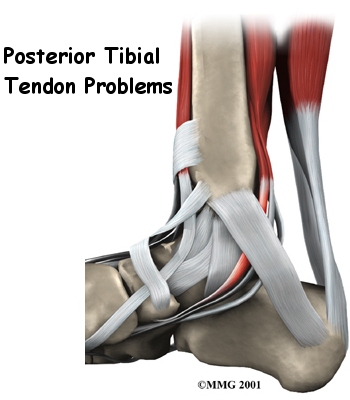

Posterior Tibial Tendon Problems Patient Guide

Due to the fact that we use our feet continuously, tendonitis in the foot is a common problem. One of the most frequently affected tendons is the posterior tibial tendon.